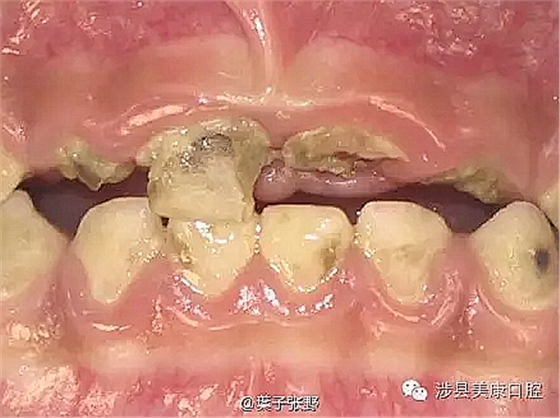

蛀牙會(huì)疼痛,非常痛。孩子可憐死了,影響吃飯。

![(VG08}R)0@])T5`)IIBPUD5.png (VG08}R)0@])T5`)IIBPUD5.png](/Mobile/UploadFiles/FCK/2017-04/6362664243054169673055611.png_280.jpg)

影響美觀,讓小朋友笑話。